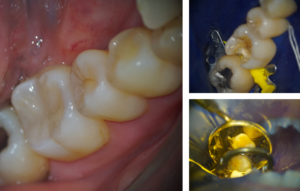

ラバーダム防湿法とマイクロスコープを使用し虫歯の除去

歯の周りをゴムで覆って湿度を限りなく下げる手法

唾液などの水分、呼吸による湿度を下げてダイレクト CRの接着力を大幅に上昇させることにより、削る歯を最小限にとどめ、治療することが可能です。

虫歯を染め出し、マイクロスコープを使用しながら虫歯だけをていねいに除去していきます。

※赤丸のようなリングを歯にかけるため、痛みがある場合など、治療箇所以外にも麻酔が必要となる場合があります。

青丸:青く染め出した虫歯

赤丸部分:亀裂